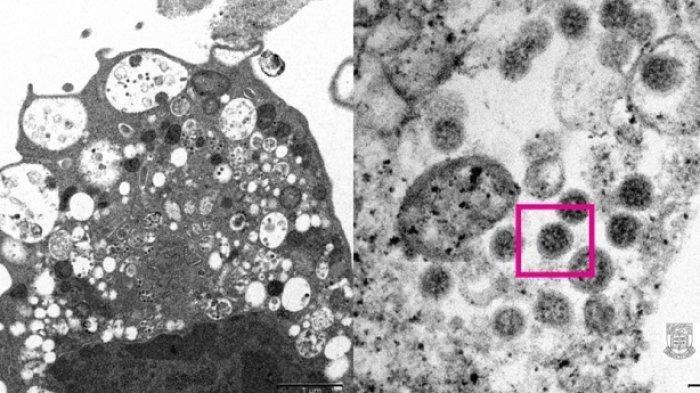

Virus Corona

Seperti diberitakan sebelumnya, Kemenkes Republik Indonesia resmi menyatakan covid-19 varian omicron telah ditemukan di Indonesia.